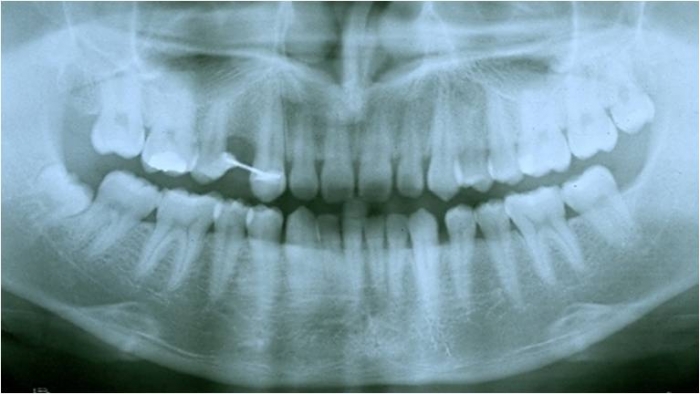

Raio X inicial